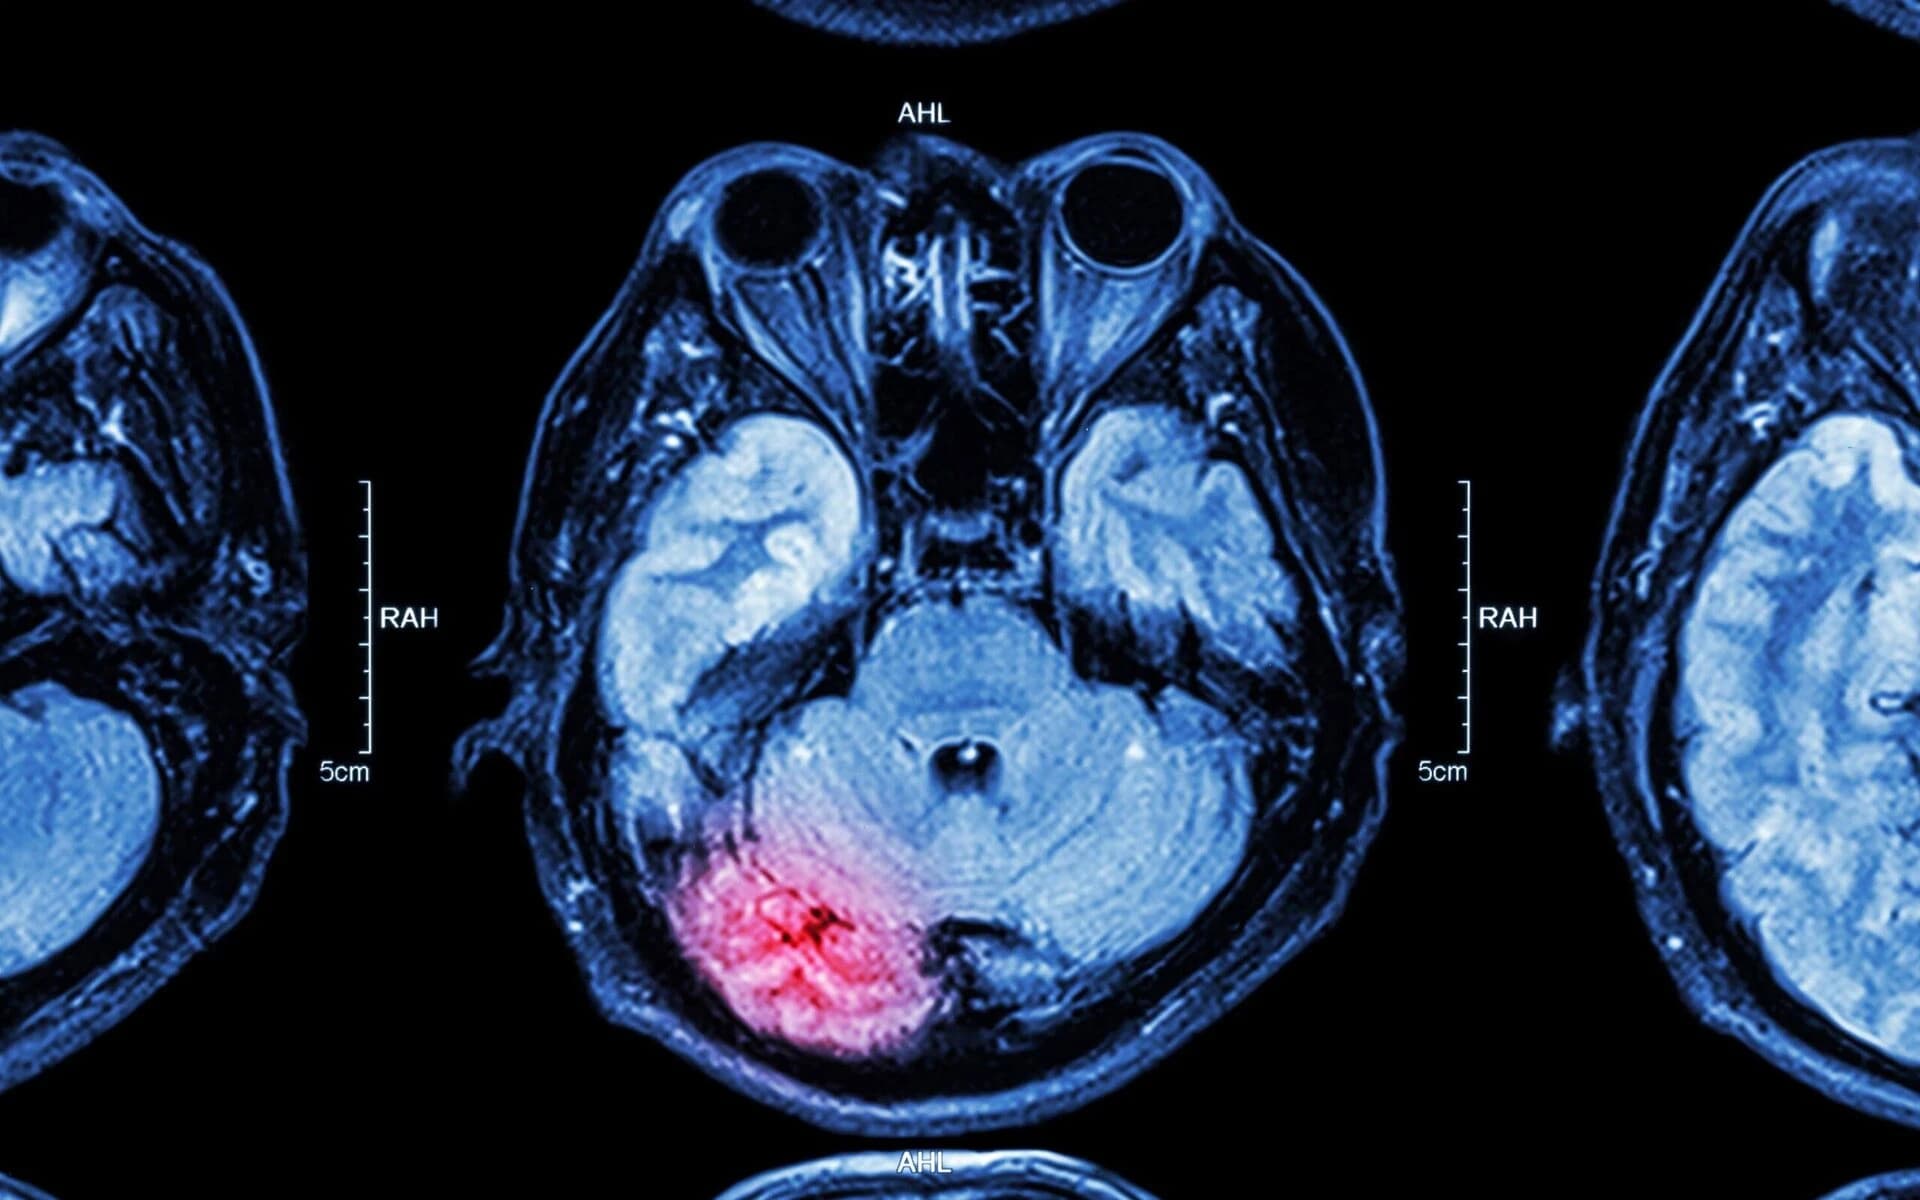

Concussions, contusions, and severe TBI from head impact.

Learn MoreTBI & concussion cases

Traumatic brain injury requiring long-term care